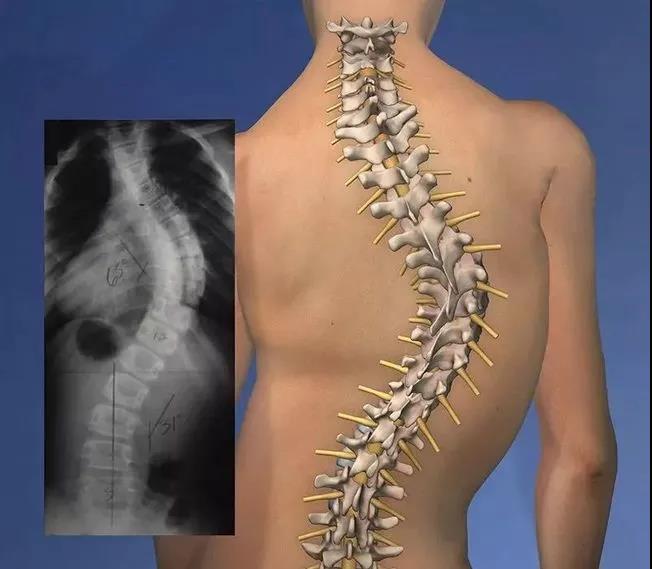

脊柱侧弯也叫脊柱侧凸,是脊柱的非正常弯曲。正常人的脊柱在肩部有向后的弯曲,从后面看是一条直线并且两侧基本对称,而脊柱侧弯则是指脊柱左右方向的一个弯曲状态。

在临床,医生会用Cobb角来进行判断,如果角度超过10度,则诊断为脊柱侧弯。

典型的脊柱侧弯包括三维的脊柱和肋骨畸形。根据度数的变化,脊柱从侧面弯曲,有时椎骨有轻微旋转,导致髋部或肩部出现不平衡。可能发展至下列情况:

主要是侧面的弯曲(类似英文字母C)或有两个弯曲(一个主要的弯曲和一个次要的弯曲,导致形成S形),脊柱侧弯最常发生在上背(胸椎区域)与下背(腰椎区域)之间。还有可能只在上或下背发生侧弯。